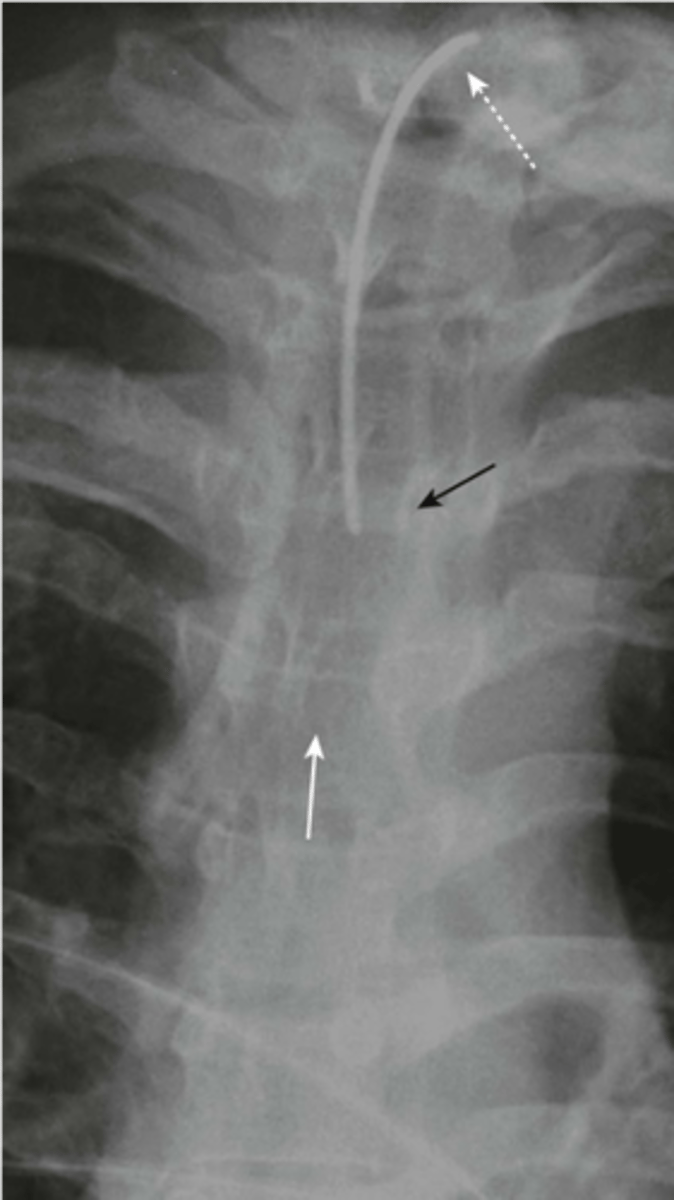

-tip halfway between stoma and carina (T3 level)

Tracheostomy tube

-tip in SVC

Central venous catheter

-hard to see

peripherally inserted central catheters

-2cm from hilum in proximal pulmonary artery

swan ganz catheter

-effusion: tip posteriorly and inferiorly

-pneumothorax: tip anteriorly and superiorly

Chest tube

tube should extend about 10cm

Nasogastric tube (NGT)

-tip should be in 2nd or 3rd portion of duodenum

dobhoff tube (DHT)